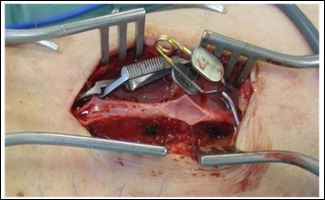

Figure 3: Trabecular, post thrombotic lesions of the cephalic vein of the upper arm.

We examined the angiography again and identified a stenosed segment of the cephalic vein at the distal upper arm. Regarding to the missing well-developed collaterals maintaining venous out flow before the fistula was at risk for occlusion. Hence, we performed surgical revision of the stenosis using an interposition graft (PTFE 6 mm). This segment showed post thrombotic lesions as well with trabecular morphology. The flow rate measured 550 ml/min and there was continuous thrill in the fistula. The temperature of the hand was warm, and pulses were palpable at the wrist.

Catheter angiography shows vascular anatomy of the fistula with out flow obstruction at the upper arm cephalicvein (Figure 3) and well-developed collaterals (Figures 1 and 4). Troubleshooting was not such as adequate as we did appreciate preexisting problems in this case. Figure 1 demonstrates primary flow is drained through the collateral in the basilic system. Figure 2 shows inadequate drainage into the deep venous system through elbow perforator with lesions in upper arm cephalic vein and non-visualization of median cubital vein.